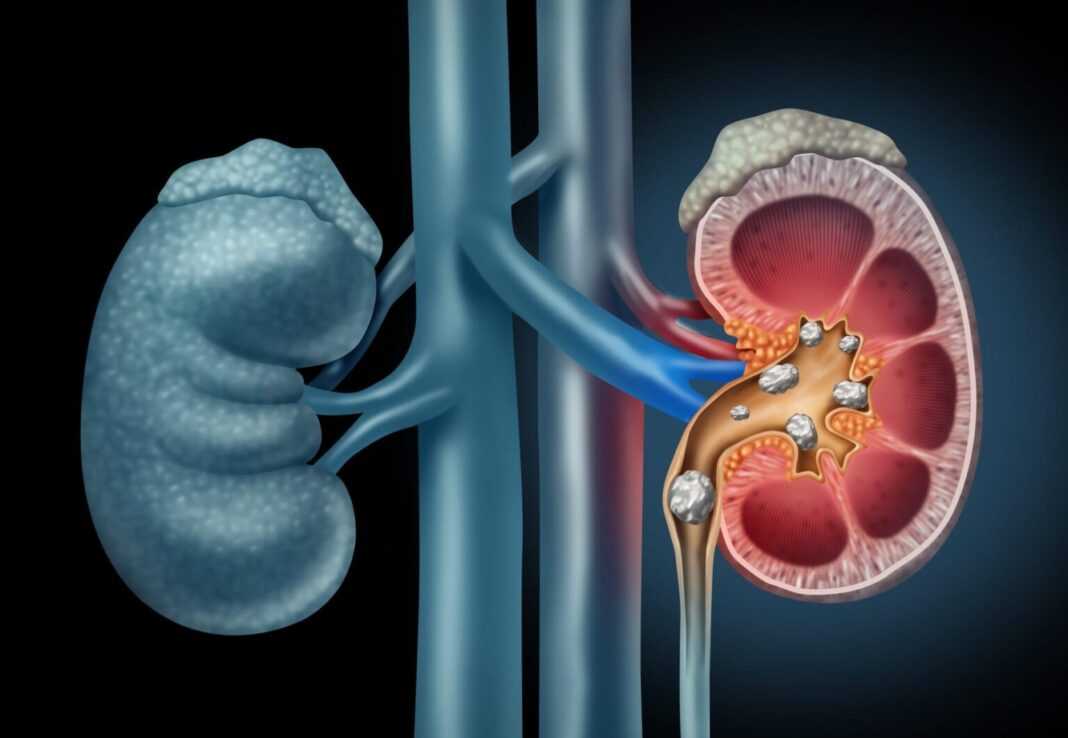

Η υπερθέρμανση του πλανήτη μπορεί να αποτελέσει απειλή για τους νεφρούς σας, σύμφωνα με νέα έρευνα. Για τη μελέτη, οι ερευνητές ανέλυσαν δεδομένα από νοσοκομεία σε περισσότερες από 1.800 πόλεις στη Βραζιλία μεταξύ 2000 και 2015 και διαπίστωσαν ότι λίγο πάνω από το 7% όλων των εισαγωγών για νεφρική νόσο θα μπορούσαν να αποδοθούν σε υψηλότερες θερμοκρασίες. Αυτό ισοδυναμεί με περισσότερες από 202.000 περιπτώσεις νεφρικής νόσου, σύμφωνα με την έκθεση που δημοσιεύτηκε στις 31 Οκτωβρίου στο περιοδικό The Lancet Regional Health – Americas.

Για κάθε 1 βαθμό Κελσίου (1,8 βαθμούς Φαρενάιτ) αύξηση της μέσης ημερήσιας θερμοκρασίας, υπήρχε σχεδόν 1% αύξηση στη νεφρική νόσο. Αυτοί που κινδυνεύουν περισσότερο ήταν γυναίκες, παιδιά κάτω των 4 ετών και άτομα ηλικίας 80 ετών και άνω. Η συσχέτιση μεταξύ της θερμοκρασίας και της νεφρικής νόσου ήταν ισχυρότερη την ημέρα της έκθεσης σε ακραίες θερμοκρασίες, αλλά διήρκεσε για μία έως δύο ημέρες μετά, διαπίστωσαν οι ερευνητές. Η μελέτη «παρέχει ισχυρές ενδείξεις ότι πρέπει να αναπτυχθούν περισσότερες πολιτικές για την πρόληψη των νοσηλειών που σχετίζονται με τη ζέστη και τον μετριασμό της κλιματικής αλλαγής», έγραψαν οι Yuming Guo και Shanshan Li, της Planetary Health στο Πανεπιστήμιο Monash στην Αυστραλία και οι συνεργάτες του.

Η μελέτη κυκλοφόρησε την Παρασκευή λίγο πριν από την έναρξη διεθνούς διάσκεψης για την κλιματική αλλαγή, που πραγματοποιήθηκε στη Σκωτία. Μια δημοσίευση του 2017 στο The Lancet, η οποία δήλωσε ότι η νεφρική νόσος αποτελεί παγκόσμια ανησυχία για τη δημόσια υγεία, ανέφερε ότι σχεδόν 2,6 εκατομμύρια θάνατοι παγκοσμίως εκείνο το έτος οφείλονταν σε διαταραχή της νεφρικής λειτουργίας. Οι θάνατοι από νεφρική νόσο είναι σχεδόν 27% υψηλότεροι από ό,τι την προηγούμενη δεκαετία, και αυτή η μελέτη δείχνει ότι η κλιματική αλλαγή ήταν ένας παράγοντας αυτής της αύξησης.